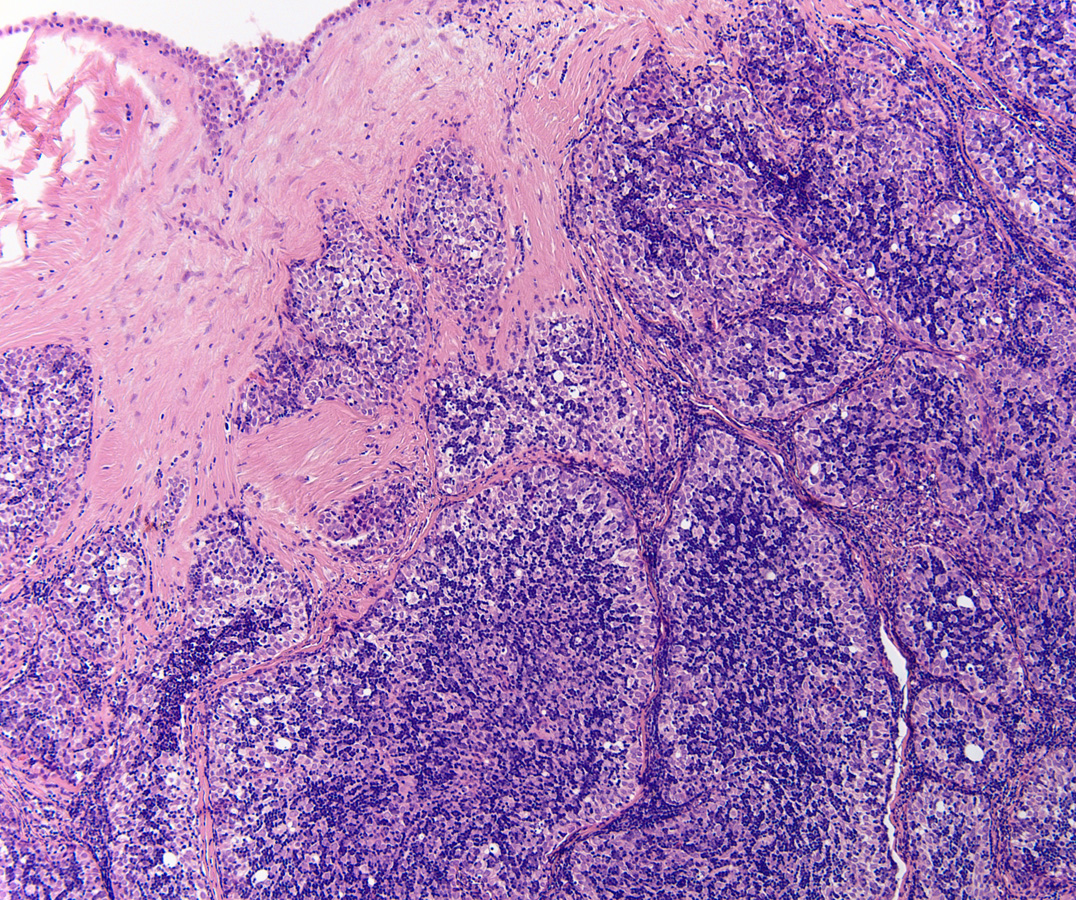

Low power H&E show tumor in below the mesothelial lining. Distinct lobular / organoid appearance noted with two types of cells, small lymphoid cells and large neoplastic cells with clear cytoplasm (bi-phasic pattern). IHC stains showed large cells are cytokeratin positive and small lymphoid cells expressed CD3, CD5 and ntDt (immature thymocytes).

Additional history later revealed a large anterior mediastinal mass with tracheal compression and seeding of pleura. Main tumor was not resectable. Histology (epithelial elements and thymic lymphoid stroma) and IHC stains support an aggressive thymoma, WHO B2, metastatic to pleura. Normal thymic milieu i.e. immature thymocytes often present in metastasis along with neoplastic epithelial component. Metastatic thymoma must be considered in the differential diagnosis with bi -phasic patten as illustrated above.